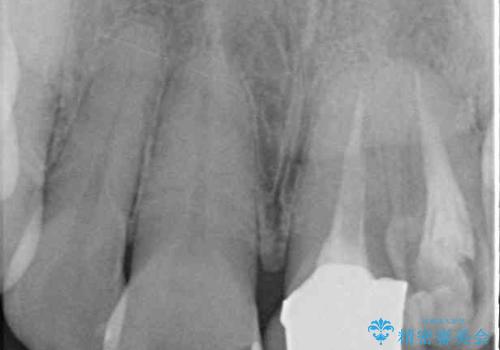

真ん中のオールセラミッククラウンを正面から見ると大変自然に仕上がっているのですが、側方から見ると白色が強く、さらには隣の歯は神経が除去されて変色していたため、コントラストでより色の違いが際立っていました。

前歯2本をオールセラミッククラウンにて補綴治療することとしました。